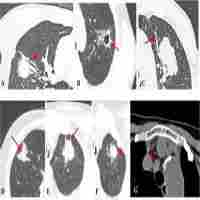

| Abstract | Objectives: To evaluate the performance of radiomic features on classifying histological subtypes of central lung cancer in contrast-enhanced CT (CECT) images. Materials and Methods: A total of 200 patients with radiologically defined central lung cancer were recruited. All patients underwent dual-phase chest CECT, and the histological subtypes (adenocarcinoma (ADC), squamous cell carcinoma (SCC), small cell lung cancer (SCLC)) were confirmed by histopathological samples. 107 features were used in five machine learning classifiers to perform the predictive analysis among three subtypes. We trained and validated models in two conditions: only using radiomic features, and combing clinical features with radiomic features. The performance of the classification models was evaluated by the area under the receiver operating characteristic curve (AUC). Results: The highest AUCs in classifying ADC vs. SCC, ADC vs. SCLC, and SCC vs. SCLC were 0.879, 0.836, 0.783, respectively by using only radiomic features by feedforward neural network. Conclusion: Our study indicates that radiomic features based on the CECT images might be a promising tool for noninvasive prediction of histological subtypes in central lung cancer and the neural network classifier might be a preferred choice to this task. |